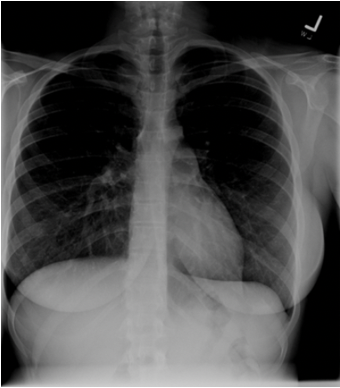

Q

How can you tell this CXR is underpenetrated?

A

• Mediastinum and spine appear white

• Left hemidiaphragm not visible to edge of spine

• Vertebrae behind the heart barely visible

• Lug tissue behind heart cannot be assessed